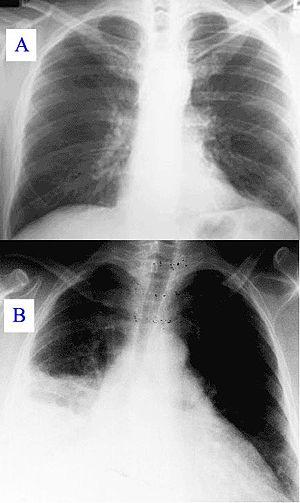

Pneumonia as seen on chest X-ray. A: Normal chest X-ray. B: Abnormal chest X-ray with consolidation from pneumonia in the right lung, middle or inferior lobe (white area, left side of image).

• Typically, an area of white lung is seen on a standard X-ray.[5] Consolidated tissue is more radio-opaque than normally aerated lung parenchyma, so that it is clearly demonstrable in radiography and on CT scans. Consolidation is often a middle-to-late stage feature/complication in pulmonary infections.